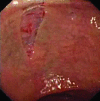

Figure 1

Superficial mucosal tear in the antrum.